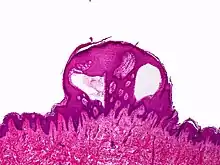

| Lymphangioma circumscriptum; only stratum papillare is affected. | |

Superficial lymphatic malformation is a congenital malformation of the superficial lymphatics, presenting as groups of deep-seated, vesicle-like papules resembling frog spawn, at birth or shortly thereafter.[1] Lymphangioma circumscriptum is the most common congenital lymphatic malformation. It is a benign condition and treatment is not required if the person who has it does not have symptoms from it.

A biopsy of the affected skin and histological examination under the microscope is necessary to diagnose lymphangioma circumscriptum.